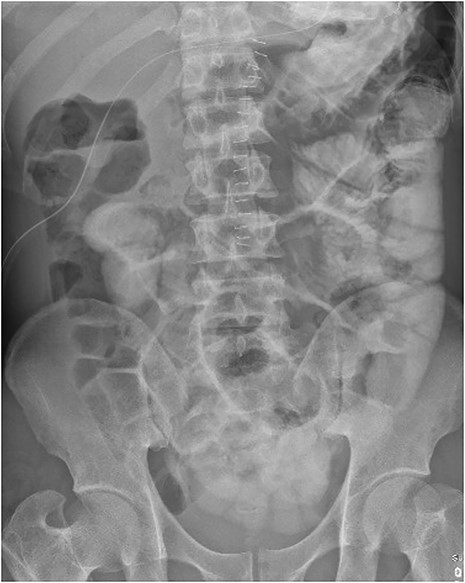

The patient was transferred to the surgical ward for ongoing cares, remaining nil by mouth and commenced on intravenous antibiotics and proton pump inhibitor infusion. On post-operative day 3, a follow-through contrast study showed no leak of enteric contents from the stomach (Fig. 3) with transit of the contrast into the duodenum, and a concurrent ileus was shown with prominent small bowel loops (Fig. 4). A clear fluid diet was initiated, with gradual upgrade before discharge to usual residence and follow-up gastroscopy as outpatient.